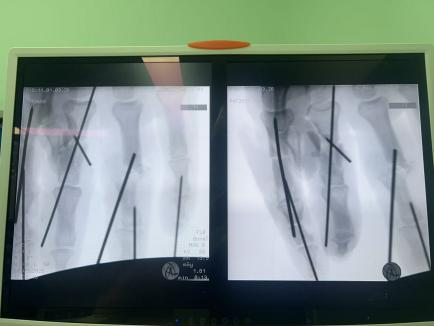

面對這些困難,許攀峰團隊沒有卻步,沉著應(yīng)戰(zhàn)。他們先是為骨折的手指進行精準內(nèi)固定,重建骨骼支撐;隨后,在顯微鏡下,一根根尋找斷裂的血管、神經(jīng)和肌腱——清創(chuàng)、修剪、吻合、通血……每一步都如履薄冰,每一次打結(jié)都需屏息凝神,手術(shù)室內(nèi),寂靜無聲,只有時鐘的滴答聲在空氣中回蕩,仿佛在為這場生命的接力默默計時。

1小時、2小時、3小時…… 時間在寂靜中流逝,顯微鏡下,一雙雙手在無聲地忙碌著,他們的動作嫻熟而精準,如同在跳一場無聲的生命舞蹈。終于,將近5個小時后,最后一針縫線完成。松開止血鉗,所有再植的手指瞬間恢復(fù)紅潤,指腹飽滿,毛細血管反應(yīng)靈敏——手術(shù)成功了!這一刻,手術(shù)室內(nèi)壓抑的氣氛瞬間被打破,許攀峰團隊成員們臉上露出了欣慰的笑容。